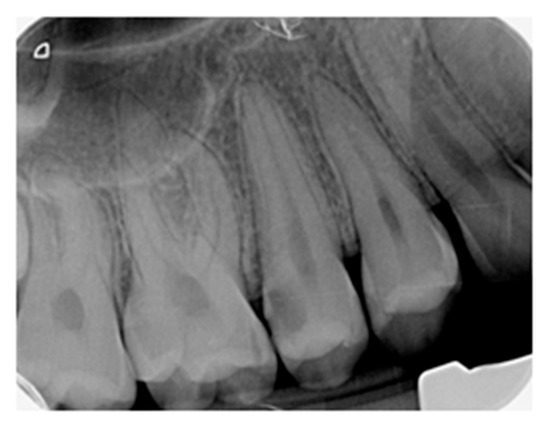

4.3. Endpoint of Carious Dentine Excavation

- Demant, S.; Dabelsteen, S.; Bjørndal, L. A macroscopic and histological analysis of radiographically well-defined deep and extremely deep carious lesions: Carious lesion characteristics as indicators of the level of bacterial penetration and pulp response. Int. Endod. J. 2021, 54, 319–330. [Google Scholar] [CrossRef]